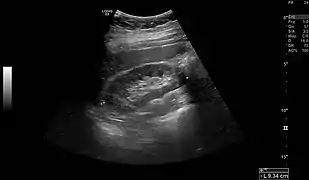

Normal adult right kidney as seen on abdominal ultrasound with a pole to pole measurement of 9.34 cm.

Renal ultrasonography is essential in the diagnosis and management of kidney-related diseases.[44] Other modalities, such as CT and MRI, should always be considered as supplementary imaging modalities in the assessment of renal disease.[44]